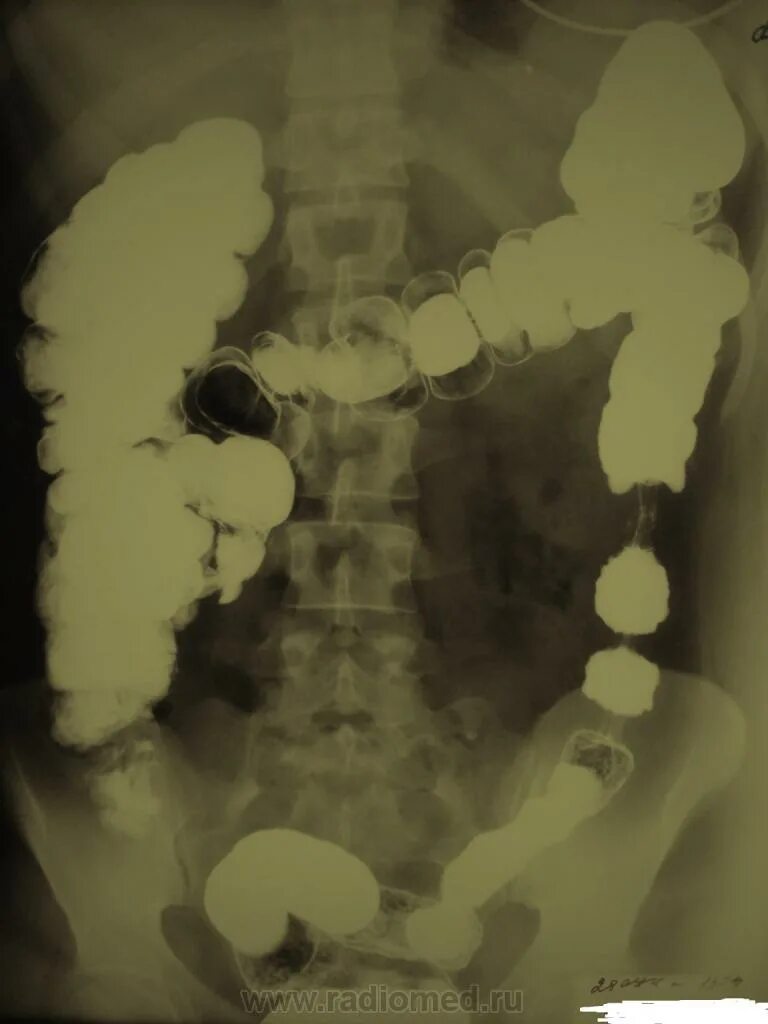

Ирригоскопия выявляет